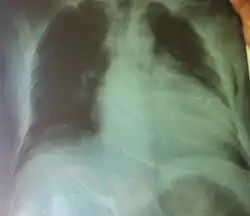

Bildgebung

Im Röntgen-Thorax ist der Herzschatten verbreitert. In der Echokardiographie und in der Kernspintomographie sieht man eine Erweiterung der Ventrikel und der Vorhöfe. Die Wand des linken Ventrikels ist meist verdünnt, der linke Ventrikel kugelig umgeformt und allseits vermindert beweglich (kontraktil).

Die Auswurffraktion ist reduziert. Der Abstand zwischen vorderem Mitralsegel und Septum ist vergrößert. Oft liegen eine Mitralklappeninsuffizienz und eine Trikuspidalklappeninsuffizienz vor.